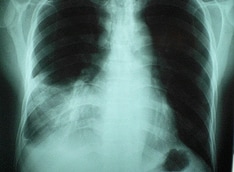

Pediatric Hypertension. Management algorithm. AMC = Apparent mineralocorticoid excess; GRA = Glucocorticoid remedial aldosteronism; VMA = Vanillylmandelic acid.